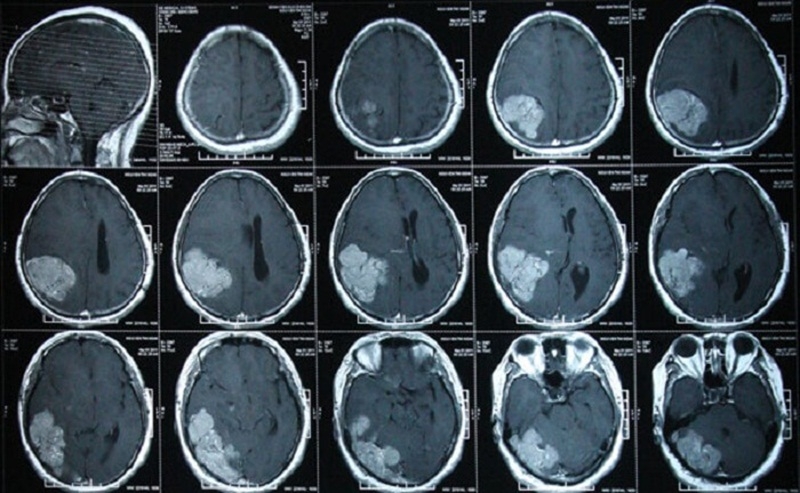

Giá chụp CT bao nhiêu tiền và ưu nhược điểm của phương pháp này-1 Khi có chỉ định chụp CT đầu thường là bệnh nhân bị chấn thương hoặc nghi ngờ liên quan đến não

Chụp CT đầu

Khi có chỉ định chụp CT đầu thường là bệnh nhân bị chấn thương hoặc có nghi ngờ dấu hiệu bệnh liên quan vùng đầu. Mục đích của việc chụp CT đầu là sử dụng tia X để tiến hành kiểm tra, đánh giá tình trạng sức khỏe của phần đầu người bệnh. Người bệnh được hướng dẫn sẽ nằm yên trên bàn y tế chuyên dụng. Các bác sĩ sẽ chiếu tia X cho nó di chuyển qua lại xung quanh vùng đầu người bệnh kết quả thu được hình ảnh 2D, 3D. Dựa trên kết quả hình ảnh bác sĩ sẽ kết luận tình trạng sức khỏe vùng đầu của bạn.